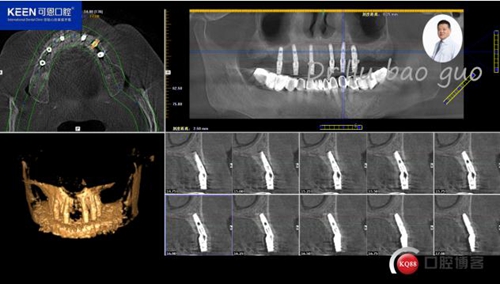

手術(shù)前種植軟件設(shè)計(jì)方案

數(shù)字化種植導(dǎo)板設(shè)計(jì)及制作